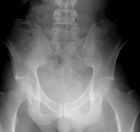

25 y/o male with chronic coccygeal pain who presents with progressive left buttock mass. Mild constipation. No other complaints. Smoker, otherwise healthy.

PE: Large, nontender mass involving L>R buttock with induration and erythema. Neurovascularly intact

Zoom image: Radiological image Radiological image.